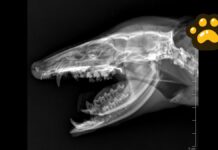

Tras darse a conocer que la noche del miércoles personal de Protección Civil Municipal de Chignahuapan realizó un recorrido donde capturaron a múltiples perros que vivían en la calle para presuntamente “llevarlos al resguardo animal”.

Ciudadanos inconformes con lo ocurrido, documentaron la forma en que, a bordo de la patrulla M-909 los ejemplares caninos eran llevados en transportadoras, sin embargo, los trabajadores del Ayuntamiento se negaron a dar mayor información sobre su actuar.